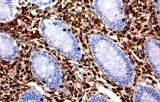

L’immunoistochimica (IHC) con anticorpi primari CE/IVD è essenziale per una diagnosi e classificazione accurata sia delle malignità ginecologiche che mammarie. Questi anticorpi consentono la rilevazione precisa di marcatori tumorali e proteine cellulari, supportando la diagnosi differenziale e guidando strategie terapeutiche personalizzate.

Gli anticorpi primari contro il recettore degli estrogeni (ER), recettore del progesterone (PR), HER2 e Ki-67 rimangono il pilastro della classificazione e delle decisioni terapeutiche nel cancro al seno. Questi anticorpi sono validati clinicamente e marcati CE/IVD per garantire una rilevazione affidabile e riproducibile dei biomarcatori – cruciale per guidare la terapia ormonale e le strategie di trattamento mirato.